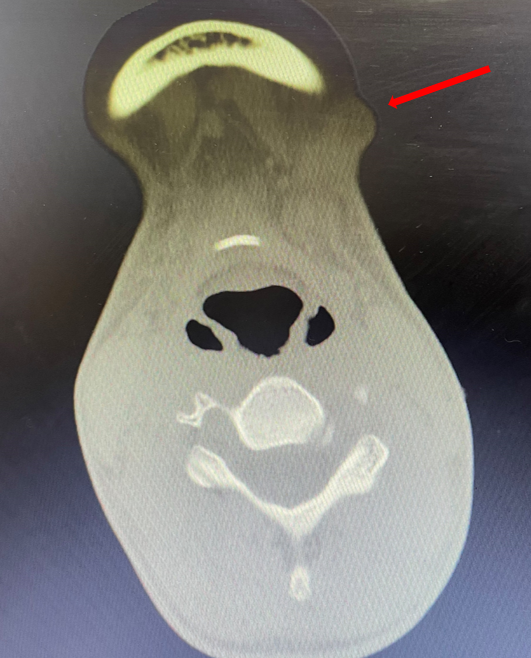

箭頭所指為頸部腫物

在完善各項(xiàng)術(shù)前檢查后,王俊文醫(yī)生對其進(jìn)行手術(shù)摘除了腫物,隨后的病理結(jié)果顯示,該患者得的是“貓抓病”。